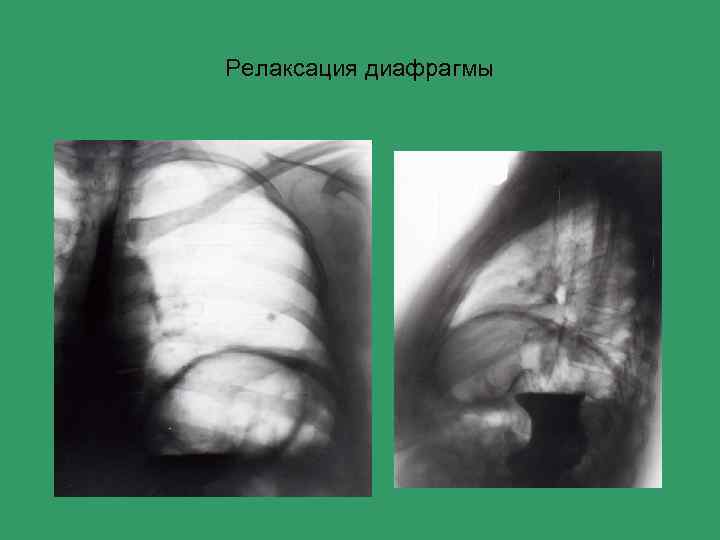

Релаксация диафрагмы